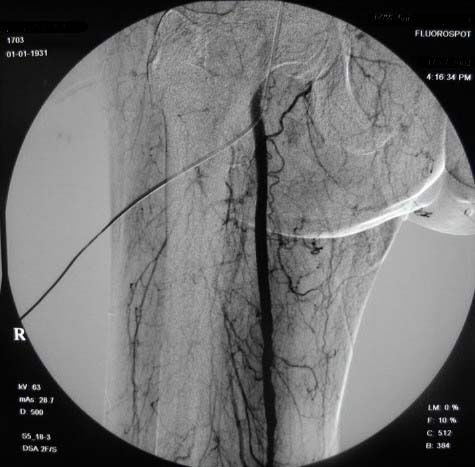

左下肢:

造影方法:取仰卧位,在局麻下,经右股动脉入路,采用改良seldingers技术,置入5f cobra导管于左髂外动脉行dsa,采集速度为2幅/秒,注射速率为6ml/秒,分节段造影;再将导管采用成襻技术放置于右侧髂外动脉,采用左侧同样的方法行dsa,术毕拔管、压迫止血约15分钟,包扎后嘱返病房,术后右足背动脉可扪及搏动。

右侧股浅动脉上、中段多处狭窄,下段闭塞。左侧股浅动脉多处狭窄,国动脉起始部狭窄。可以用球囊扩张配合动脉内溶栓或股浅动脉支架置入。多为糖尿病所致。